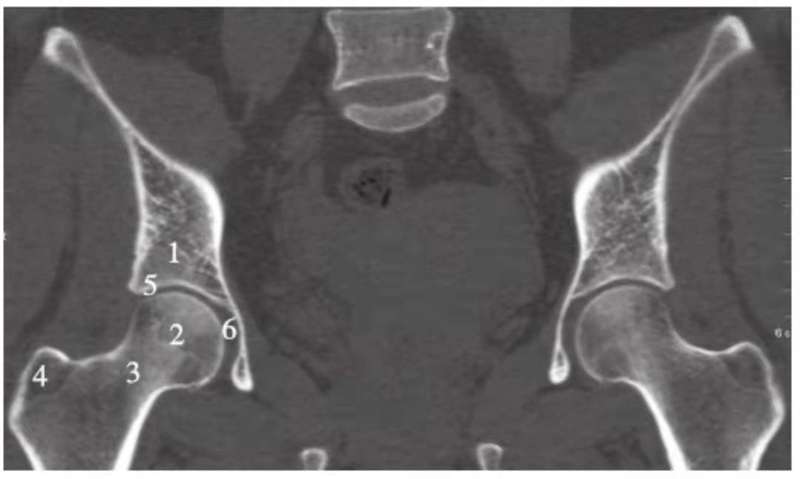

冠状位重建

图7 髋关节冠状位重建

1.髂骨;2.股骨头;3.股骨颈;4.大转子;5.髋臼;6.髋臼窝